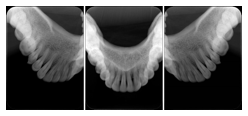

2 Occlusal Vertical Maxilla A Dental Image Layout

DL-C001A

Reference: DL-C001-U1L0

Reference: DL-C001-U2L0

2 Occlusal Vertical Mandible A Dental Image Layout

DL-C002A

Reference: DL-C002-U0L1

Reference: DL-C002A-U0L2

2 Occlusal Horizontal Maxilla A Dental Image Layout

DL-C003A

Reference: DL-C003-U1L0

Reference: DL-C003-U2L0

2 Occlusal Horizontal Mandible A Dental Image Layout

DL-C004A

Reference: DL-C004-U0L1

Reference: DL-C004-U0L2